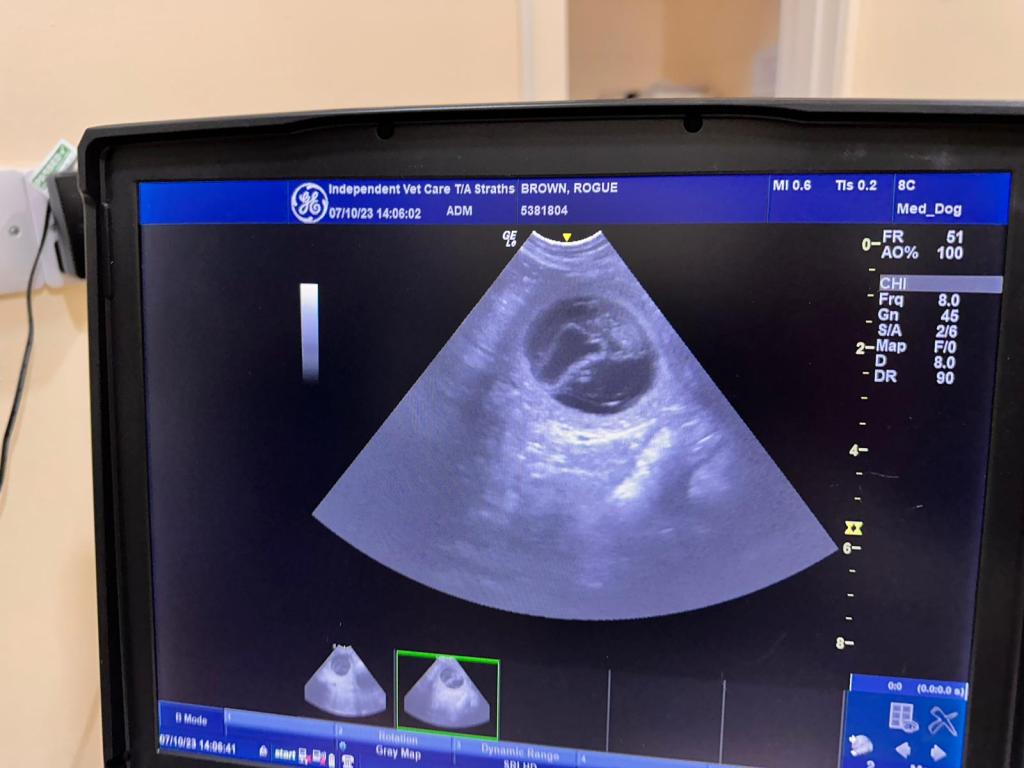

Pregnancy Confirmed! October 6, 2023avonwolf Leave a comment Rogue is pregnant which means the M-litter is happening 🥳🍾 Share this: Share on X (Opens in new window) X Share on Facebook (Opens in new window) Facebook Like Loading... Related